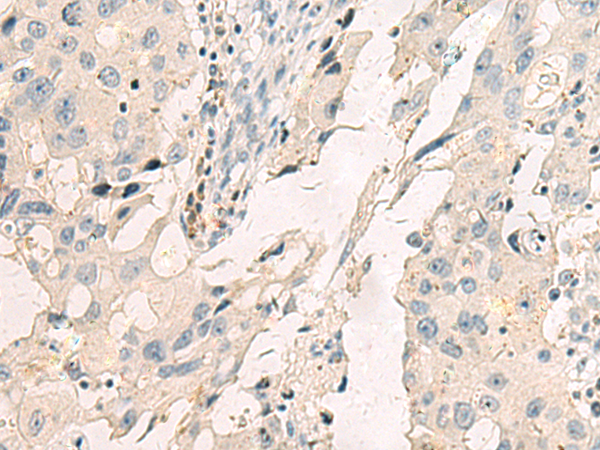

IHC positive control: |

Human breast cancer |

IHC Recommend dilution: |

25-50 |